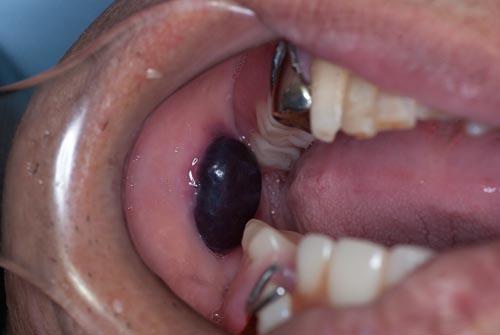

| 真ん中の赤い球状の物は、血腫です。いわゆる「血豆」ですが、口腔内にもできます。間違って頬粘膜を咬んだためにできたのですが、この様に歯と同じ位の大きさになる事があります。このままですとじゃまですし、さらに大きくなる可能性がありますので、切開して中の血液を排出させます。すぐにすっきりと楽になり、傷も数日で治ります。 | ![]() |

| これも血腫ですが、今まで私が見た中で一番大きい物ですね。 | ![]() |